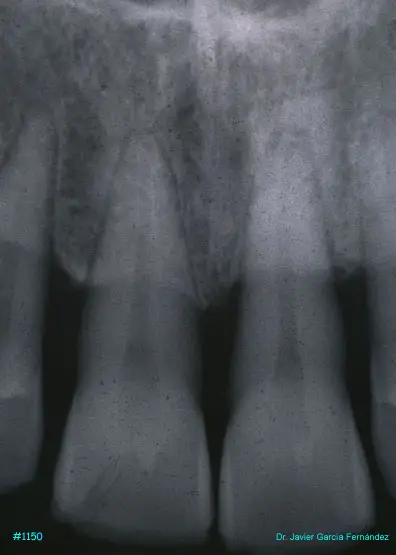

Atlas of Surgical Techniques in Periodontics. Chapter III. Atlas de Técnicas Quirúrgicas en Periodoncia